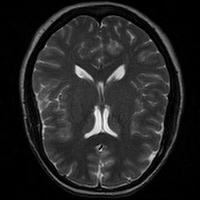

4.4 Qualitative Evaluation

In Figure 5 we analyze the prediction quality of our and compared approaches in a qualitative way. Considering modality propagation in MRI, we see that usage of uncertainty-aware patch invariance (UAPI) gives a better detailed weighting of the cerebrospinal fluid in the middle of the brain. In general, employing patch invariance yields better preservation of fine structures. This observation also applies to accelerated MRI enhancement. In particular, CUT and UAPI provide comparatively sharper knee images with more high-frequency details than the other methods.